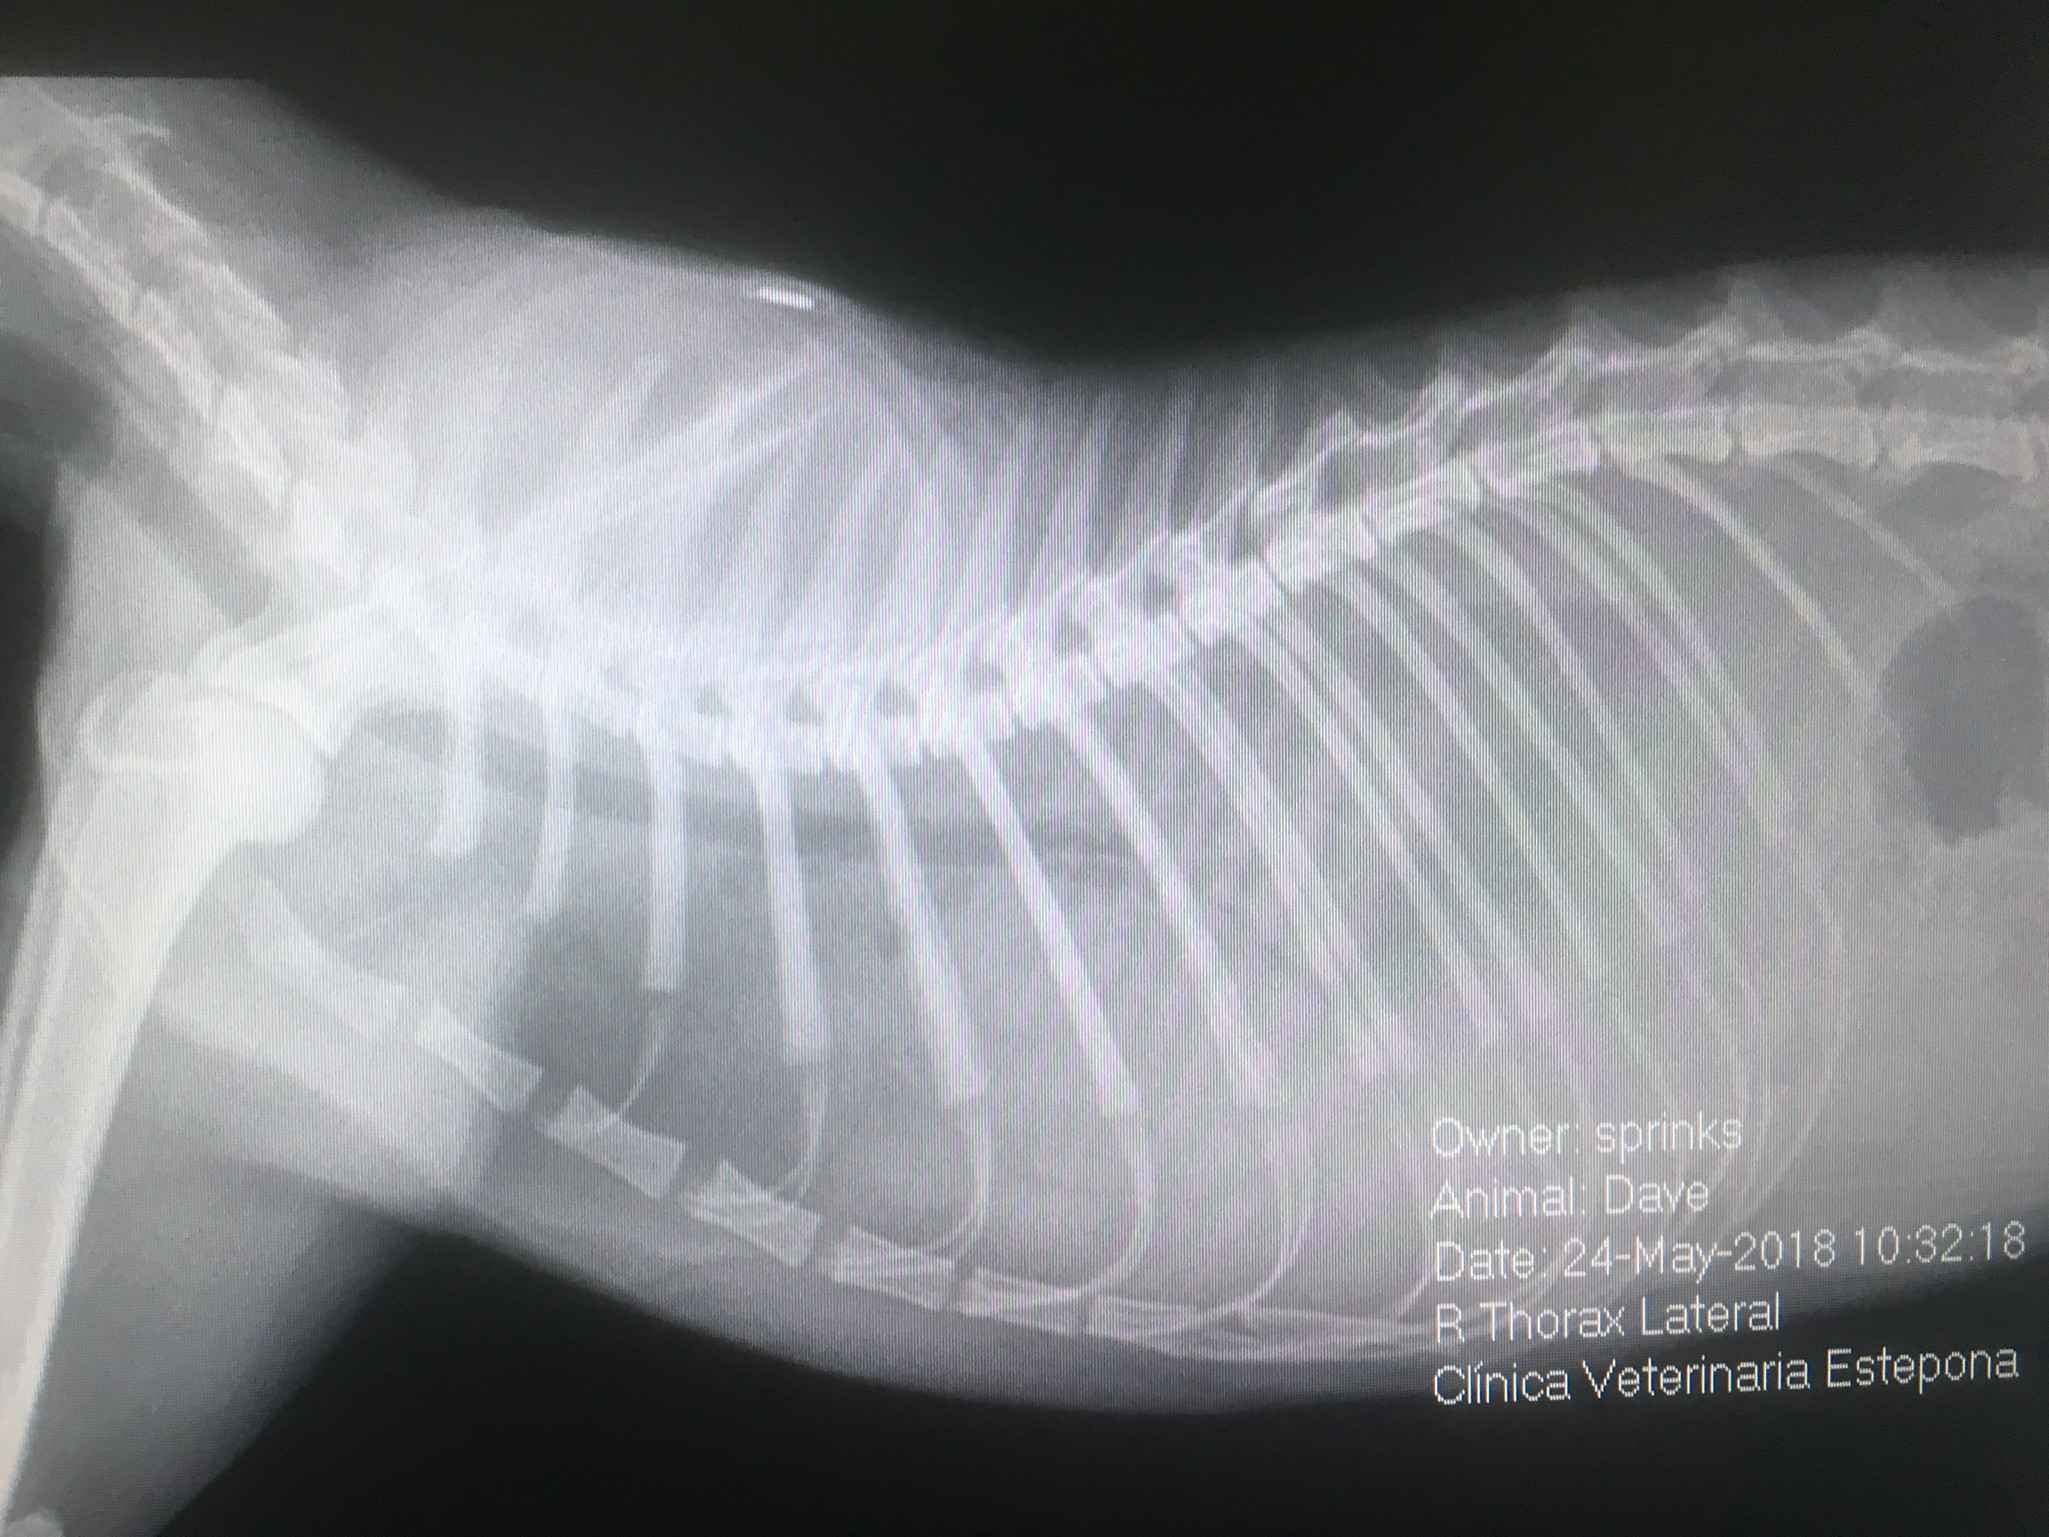

Así, la Radiología Digital y la Ecografía de alta definición, son piezas fundamentales para lograrlo, junto a un minucioso examen clínico.

En la Clínica Veterinaria Estepona no solo nos apoyamos en la radiología clásica, sino también en la contrastada, de tal manera que pueden realizarse estudios radiográficos especializados como:

Mielografías (para el diagnóstico de patologías de la médula espinal), Urografías y Cistografías de contraste positivo o doble contraste (para el diagnóstico de problemas renales y urinarios), y estudios de contraste digestivos (para problemas gastrointestinales), entre otros.